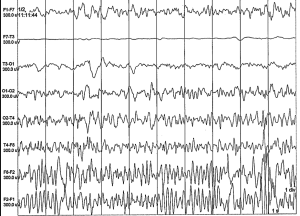

Take our EEG Test Questions!

Are you prepping for your EEG boards? 🧠📚

Do you just like engaging in posts about the NDT field? ✔

Engage with our community and enhance your knowledge in the neurodiagnostic field with our EEG Fun Facts. Each fact comes with a question and multiple choice answer to choose from to test your knowledge!